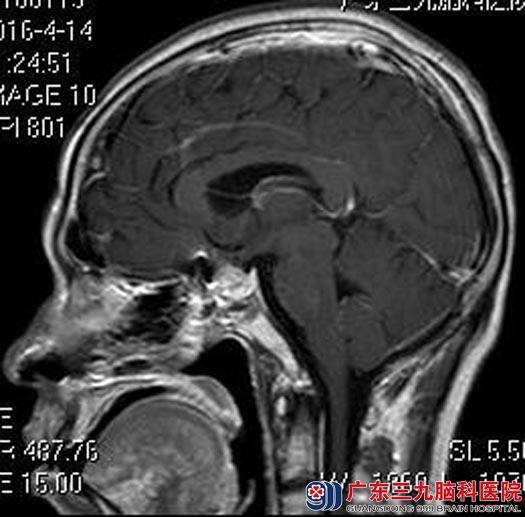

入住广东三九脑科医院垂体瘤诊疗中心,完善各项检查,由鲁明主任主刀在全麻内镜下经鼻行蝶鞍区垂体腺瘤切除术,进入蝶窦后,见鞍底完整。刮除窦内粘膜。导航再次定位,全层切开肿瘤膜,清除全部肿瘤组织,用脑膜补片修复鞍底。没有出现术后并发症,十天后即出院。

▲术后MR